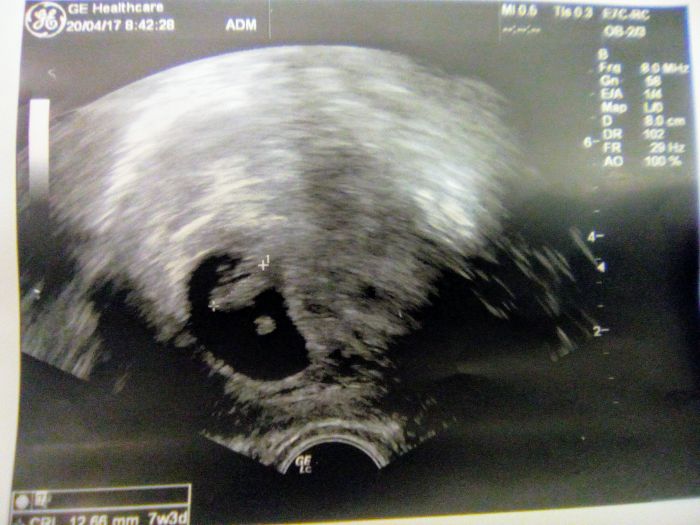

Holky, tak kontrola v CARu za mnou, vse ok, srdicko bije, odpovida 7+3 :-)

Petko, super, gratuluji. Krasny ultrazvuk :-)